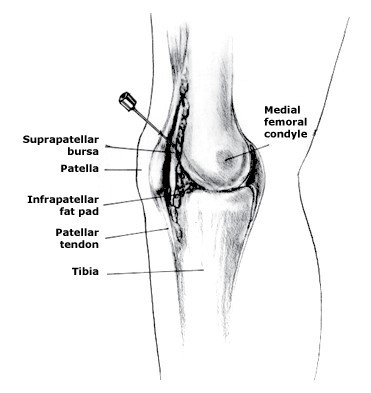

打封闭针,也就是“封闭治疗”,是将一定浓度和数量的药物注射于软组织及关节腔的痛点部位(主要是例如肌肉、筋膜、肌腱、关节滑囊等),起到消炎止痛,解除痉挛等作用。“打封闭”起源于前苏联,最早是将普鲁卡因注射于人体的局部痛点, 以起到暂时止痛的作用”。实际上“封闭”治疗炎症和疼痛,属于是“神经阻滞治疗”中的一种方法,也曾经被视为狭义的“神经阻滞治疗”。

人体的骨、关节、肌腱、肌、韧带、筋膜、滑囊及其相关的血管、神经等,对长期、反复、持续的姿势或职业动作在局部形成慢性损伤,这些损伤会引发局部的炎症,这样的炎症状态就会表现为受损的部位发红、肿胀、发热并且产生疼痛。这种疼痛多为无菌性炎症(非细菌、病毒等微生物引发的感染性炎症)所致,严重时会影响我们的工作和生活。这种慢性炎症会引发受损组织自我修复,而炎症部位修复的“矫枉过正”就是“增生”,骨组织炎症后修复所导致的增生被称之为“骨质增生”,而骨刺,就是骨质增生的俗称,是常见的骨科疾病。引起骨质增生病因有很多,并非只有老年人才会罹患,年轻人也会有,比如青年运动员长期运动劳损引发的骨质增生。

骨刺本身不会消除(手术清除除外),但是骨刺也并非是组织正常状态,所以当骨刺引发慢性炎症急性加重,伴随着难以忍受的疼痛时,医师可能就要考虑使用以改善炎症控制疼痛为目的“封闭治疗”了。